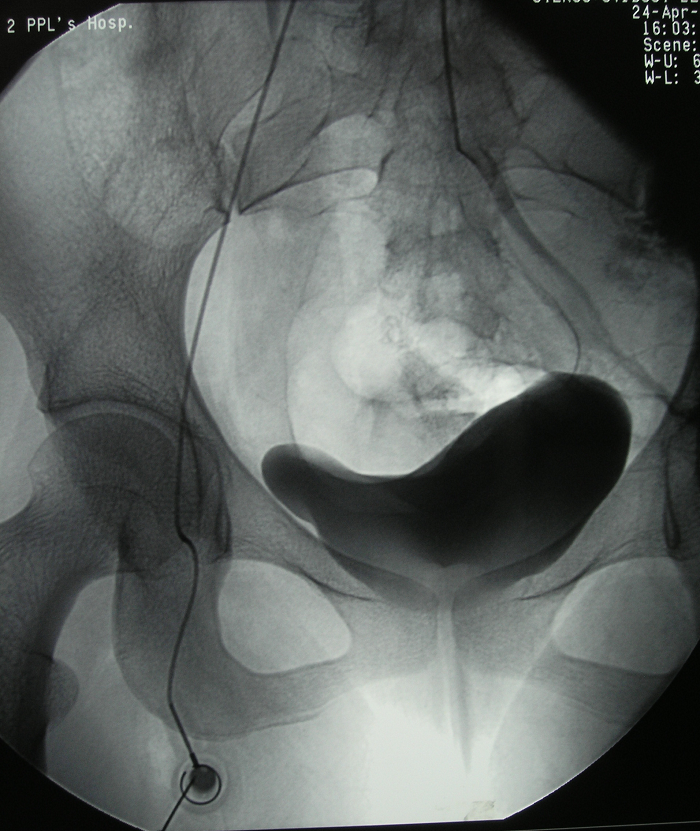

图8 术前DSA

6、病例6:女 18岁 左半骨盆骨肉瘤,全身及肿瘤局部选择性动脉灌注大剂量化疗后行肿瘤切除人工半骨盆假体置换术

图 33 术前X线片

图 34、35、36 术前CT:肿瘤体积巨大,压迫

输尿管、膀胱等盆腔脏器

图 37 术前MRI

图 38 术前ECT

图 39 术前DSA

图 40 术前动脉化疗装置